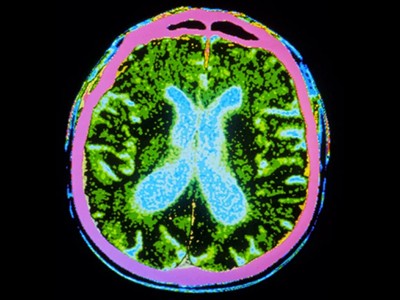

圖1:帕金森病的干細(xì)胞療法。

帕金森病是由于大腦中釋放多巴胺(多巴胺能)神經(jīng)元逐漸喪失所致。Sawamoto 等人1和 Tabar 等人2進(jìn)行了一項(xiàng)基于干細(xì)胞治療的臨床試驗(yàn)。兩個團(tuán)隊(duì)都使用了臨床級多能干細(xì)胞來補(bǔ)充多巴胺能神經(jīng)元,這種細(xì)胞可以無限分裂并分化為任何細(xì)胞類型。Sawamoto等人使用了源自健康成年捐贈者細(xì)胞的誘導(dǎo)多能干細(xì)胞系,而Tabar等人使用了源自早期胚胎的人類胚胎干細(xì)胞系。干細(xì)胞經(jīng)過培養(yǎng),形成多巴胺能神經(jīng)元祖細(xì)胞。這些細(xì)胞被移植到稱為殼核的大腦區(qū)域,殼核與尾狀核一起形成紋狀體。紋狀體與黑質(zhì)相連,而黑質(zhì)是多巴胺能神經(jīng)元損失最為嚴(yán)重的部位。早期(I/II期)臨床試驗(yàn)主要證實(shí)了該療法的安全性,同時也表明其在改善癥狀方面具有一定有效性。